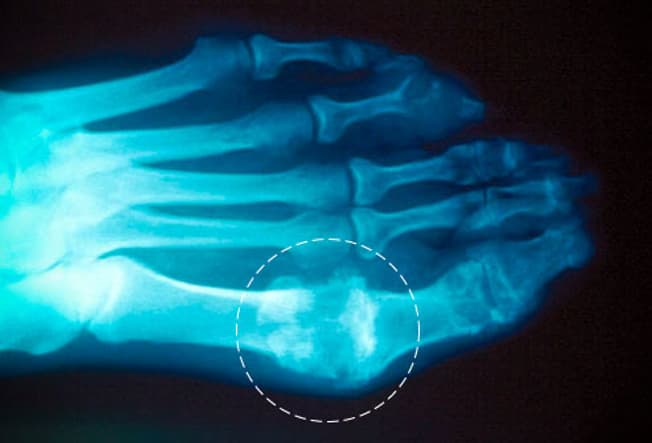

Asam urat tersebut masih berada dalam darah, sehingga orang tersebut mengalami hiperurisemia, kadar asam urat yang tinggi di dalam darah. Asam urat yang tinggi tersebut pada akhirnya bisa membentuk kristal di persendian yang dikenal sebagai Gout yang menimbulkan nyeri di persendian, bisa juga menyebabkan pengendapan berupa kristal di ginjal atau saluran kemih, sehingga memicu batu ginjal (dari jenis kristal asam urat), juga bisa menimbulkan sumbatan di ginjal sehingga menyebabkan gagal ginjal.

Gejala yang sering dialami penderita kristal asam urat akut pada area yang dikeluhkan berupa:

• Nyeri yang muncul cepat di persendian.

• Pembengkakan.

• Teraba hangat.

• Kemerahan.

• Nyeri bila ditekan.

• Biasanya persendian pada ibu jari kaki sering muncul keluhan di atas.